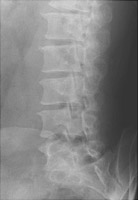

Spondylolysis refers to failure of fusion of the pars interarticularis, most often at the lower lumbar spine. This is usually a congenital defect, although it may occasionally be post-traumatic. The process may affect one or both sides of the spine. Oblique radiographs are best for the detection of this abnormality.

- Click on the image for a larger versionBOpposite oblique radiograph of the lumbar spine. This shows another pars defect at L5-S1.